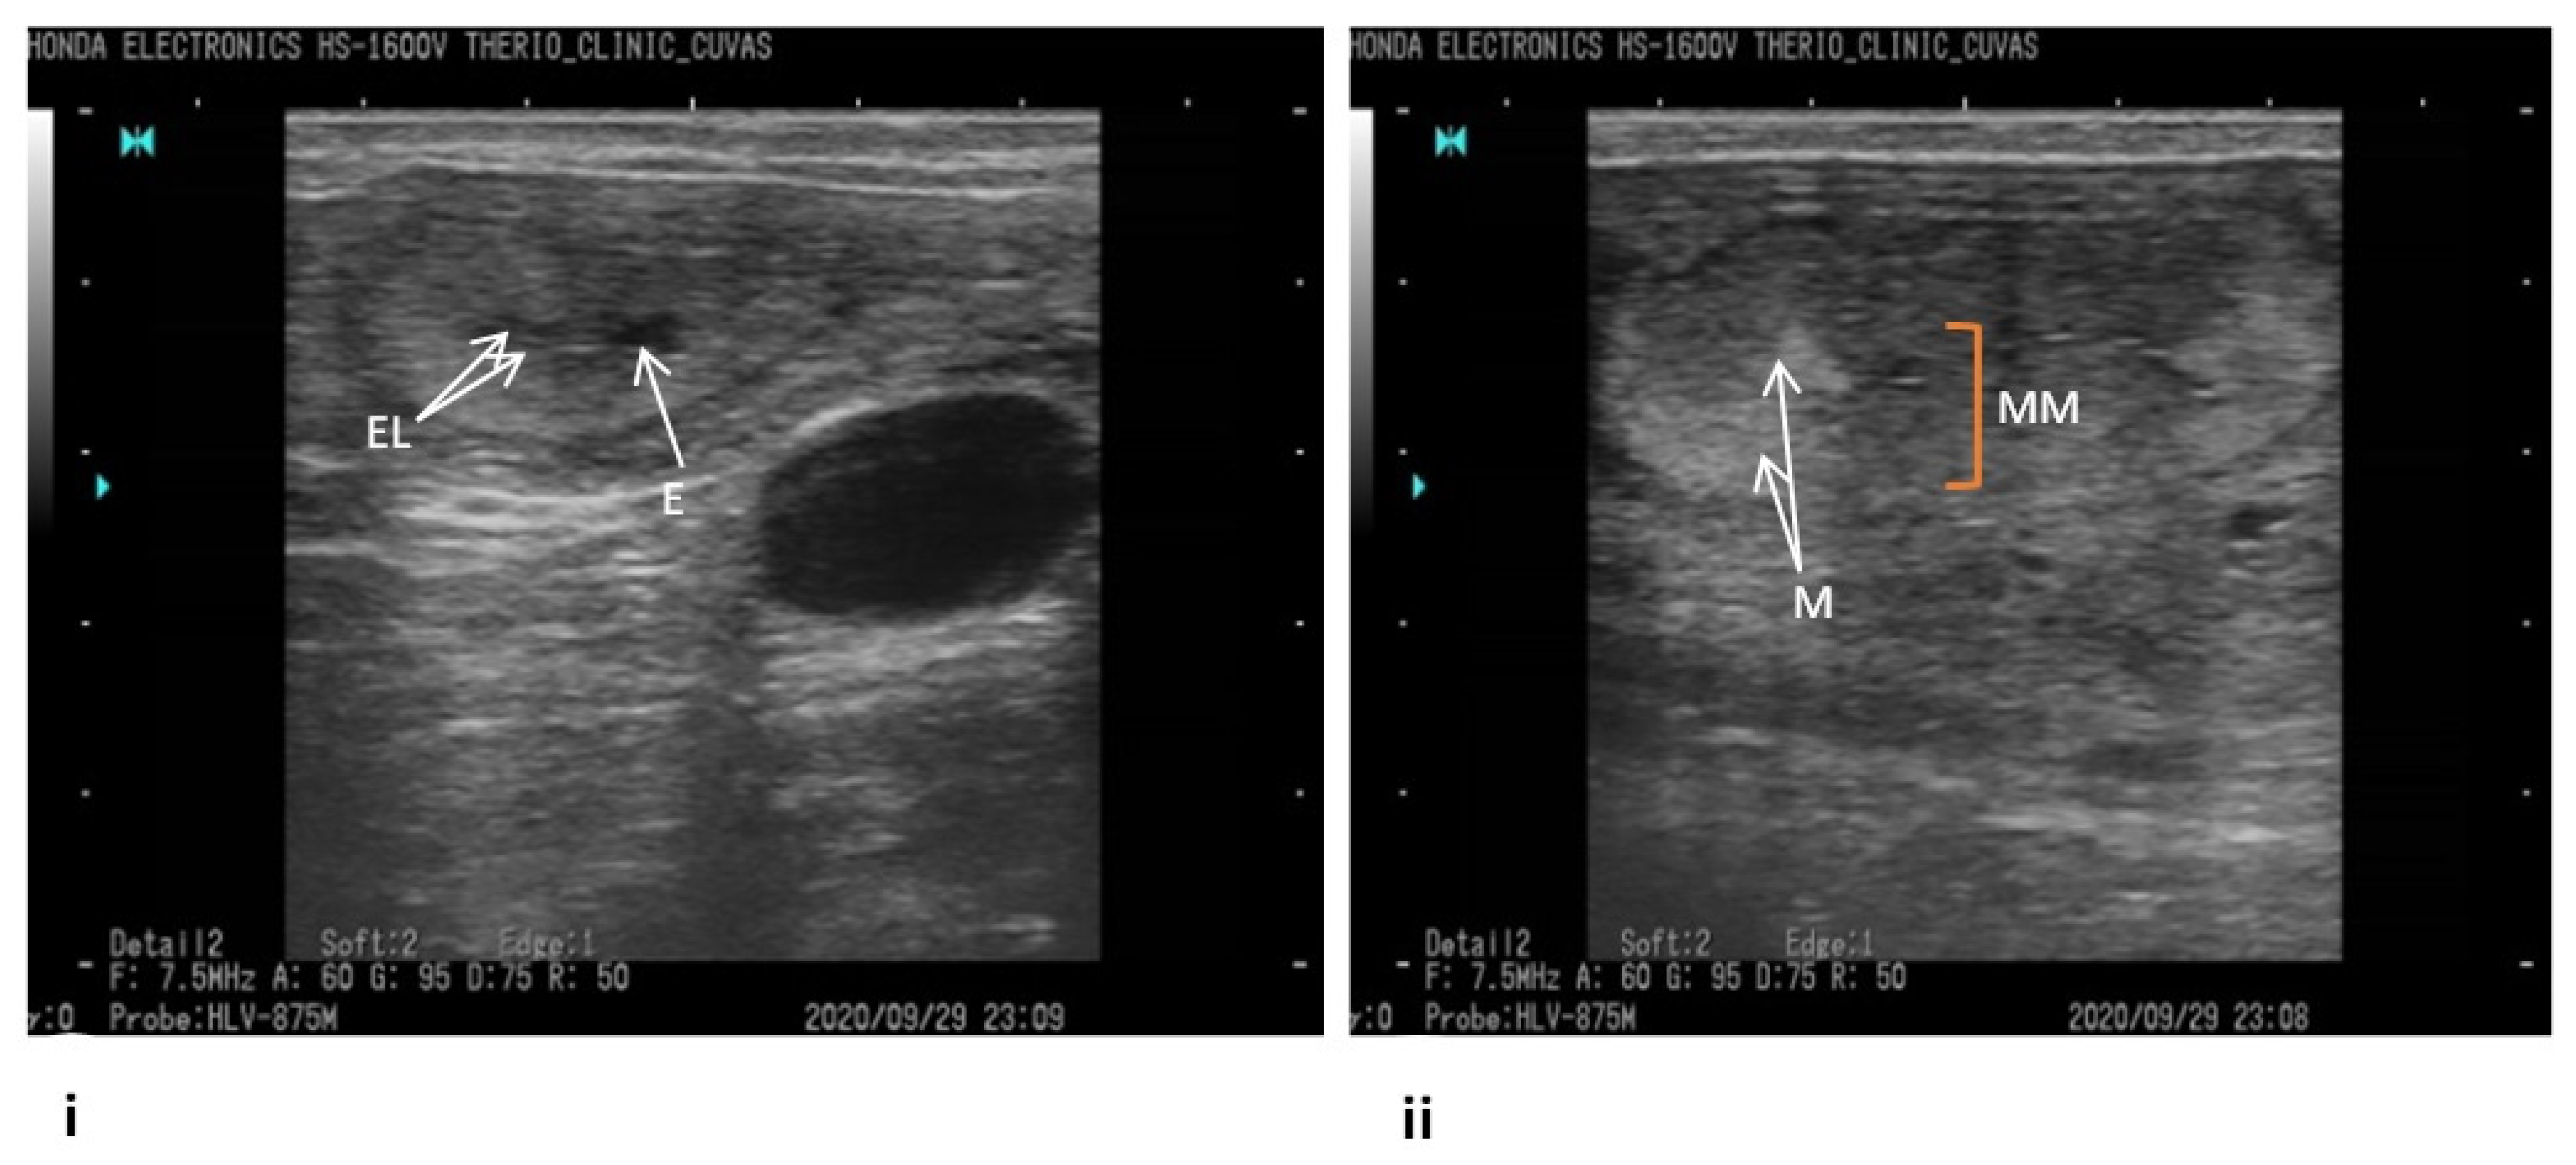

- Fissore, R.A.; Edmondson, A.J.; Pashen, R.L.; Bondurant, R.H. The use of ultrasonography for the study of the bovine reproductive tract. II. Non-pregnant, pregnant and pathological conditions of the uterus. Anim. Reprod. Sci. 1986, 12, 167–177. [Google Scholar] [CrossRef]

- Pierson, R.A.; Ginther, O.J. Ultrasonic imaging of the ovaries and uterus in cattle. Theriogenology 1988, 29, 21–37. [Google Scholar] [CrossRef]

- Ihnatsenka, B.; Boezaart, A.P. Ultrasound: Basic understanding and learning the language. Int. J. Shoulder Surg. 2010, 4, 55. [Google Scholar]